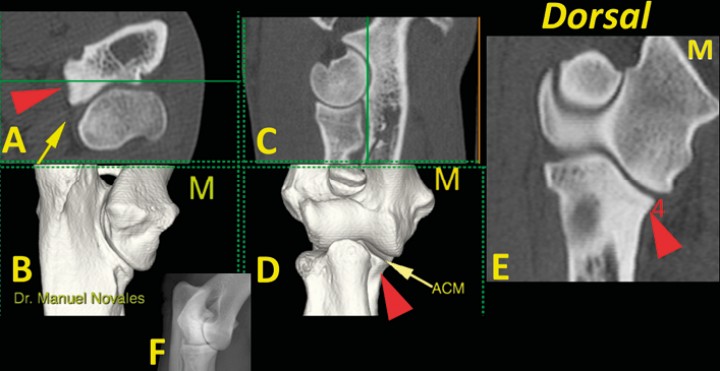

Figura 7

Codo normal. Imágenes tridimensionales del codo en visión caudomedial (B) y craneal (D), así como planos de corte transversal (A), sagital (C) y dorsal (E). Las líneas verdes en A y C muestran el nivel al que se ha producido el plano dorsal (E). Se señala una escotadura normal (punta de flecha roja) que aparece en la porción medial de la ACM (flecha amarilla) (M: lado medial).

Figura 8

Codo normal. Imágenes tridimensionales del codo en visión caudomedial (B) y craneal (D), así como planos de corte transversal (A), sagital (C) y dorsal (E). Las líneas verdes en A y C muestran el nivel al que se ha producido el plano dorsal (E). La punta de flecha roja señala la concavidad de la cara medial de la ACM (flecha amarilla) que debe ser de contorno liso (4). Se incluye una radiografía de codo en proyección craneomedial-caudolateral (F) para comparación. (M: lado medial).